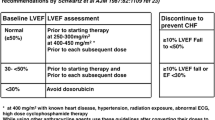

Various terminologies and definitions have been used to define CTRCD across guidelines and clinical trials [22]. This discrepancy in definitions has resulted in diagnostic and treatment disparities [11]. In the expert consensus paper from the imaging societies including the European Association of Cardiovascular Imaging/American Society of Echocardiography (EACVI/ASE), CTRCD was defined as a decrease in the left ventricular ejection fraction (LVEF) > 10 percentage points to a value < 53% (normal reference value for two-dimensional [2D] TTE) in 2014 [23]. However, in the 2016 ESC Cardio-Oncology Position Paper, CTRCD was defined as any decrease in LVEF to < 50% or a > 10% reduction from baseline to less than the lower limit of normal [24]. In recent oncology society guidelines, such as the European Society of Medical Oncology (ESMO) consensus, CTRCD was defined as an absolute LVEF decrease > 10% to < 50% or an absolute LVEF > 20% or symptomatic heart failure (HF). In such cases, cardioprotective therapy and first-line chemotherapy with cardio-oncology input and/or noncardiotoxic second-line cancer treatments should be considered [25]. Considering that LVEF has a low sensitivity to subclinical changes in heart function brought on by early myocyte damage caused by cardiotoxic treatments, LV global longitudinal strain (GLS) has been introduced to detect CTRCD. In the ESMO guideline, normal LVEF with a decrease in average GLS from baseline assessment (≥ 12% relative decrease or ≥ 5% absolute decrease) was recommended as a threshold for initiation of cardioprotective treatments. Meanwhile, the ESC and EACVI/ASE position statements defined CTRCD as a relative reduction in GLS > 15% from baseline.

To clarify the definition of CTRCD, the ESC 2022 Guidelines standardized the definition of CTRCD and introduced a classification system dividing it into symptomatic and asymptomatic categories [10]. Symptomatic CTRCD is further categorized into mild, moderate, severe, and very severe according to the need for HF treatment. Asymptomatic CTRCD is classified as mild, moderate, or severe, with mild CTRCD defined as LVEF ≥ 50% and a new relative decrease in GLS by > 15% from baseline and/or a new increase in levels of cardiac biomarkers. Severe CTRCD is defined as a new LVEF reduction to < 40%. Moderate CTRCD is defined as a new LVEF reduction by ≥ 10 percentage points to a value of 40% to 49% or a new LVEF reduction by < 10 percentage points to a value of 40% to 49%, combined with either a new relative decrease in GLS by > 15% from baseline or a new increase in cardiac biomarker levels.

Taken together and considering the measurement variability in 2D TTE (up to 10%) and agreement across professional guidelines, these results underlie a definition of CTRCD as a decrease in LVEF greater than 10% from baseline (Table 1). In cases where the follow-up LVEF is ≥ 50%, a reduction in GLS of > 15% from baseline or a new increase in cardiac biomarker levels should be present to avoid unnecessary alterations or cessation of cancer treatment. In addition, a relative decrease in LV GLS > 15% from baseline should be defined as CTRCD regardless of the change in LVEF. In addition, since an LVEF less than 40% is HF with reduced ejection fraction and requires HF treatment, any new LVEF reduction below 40% should be considered as CTRCD. Finally, patients exhibiting any symptoms or signs that meet HF diagnosis criteria according to the 2021 ESC Guidelines for the diagnosis and treatment of acute and chronic HF should also be classified as CTRCD [26]. Cardinal symptoms for HF include shortness of breath, ankle swelling, and fatigue, while signs of HF include elevated jugular venous pressure, pulmonary crackles, and peripheral edema. In addition, for individuals who exhibit a decrease in LVEF > 10% and relative reduction in GLS < 15% from baseline or with LVEF ≥ 50%, short-term TTE should be performed within 3 months. This approach is recommended as these patients are considered at elevated risk of CTRCD.

In patients with HER2-positive breast cancer, HER2-targeted therapies have been widely used in neoadjuvant, adjuvant, and palliative settings. HER2-targeted therapies have also been used in non–breast cancer patients. Regardless of cancer type, anti-HER2 therapies cause LV dysfunction in 15% to 20% of patients, which can progress to overt HF if not monitored properly. Thus, LV function surveillance including assessment of LVEF and LV GLS is recommended prior to and every 3 months during treatment.

Baseline TTE and follow-up surveillance TTE every 3 months and within 12 months after completing treatment are recommended in most professional guidelines in all breast cancer patients who received HER2-targeted therapy. In patients with palliative HER2-targeted therapy, TTE is recommended every 3 months during the first year, but the surveillance schedule can be reduced to every 6 months for future treatments. Measurement of cardiac biomarkers including cTn and NT-proBNP is recommended only in high- and very high-risk patients prior to anti-HER2-targeted therapies as a class I indication.